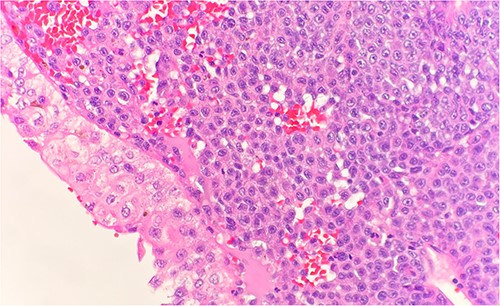

Microscopic examination shows extensive involvement of the bladder wall by sheets of small round blue tumor cells showing cleaved and irregular nuclear contours and conspicuous nucleoli. Mitotic activity is frequent and majority of cells show scant amphophilic cytoplasm with few foci showing more abundant bubbly cytoplasm and others with clear foamy cytoplasm (Fig. 1). A rare foci of finely granular brown pigment representing melanin and moderate cytological atypia in a small area of surface urothelium. Similar morphological features are seen in colonic biopsy specimens (Fig. 2).

Microscopic examination reveals sheets of round cell beneath unremarkable urothelium epithelium. H&E stain 40×.